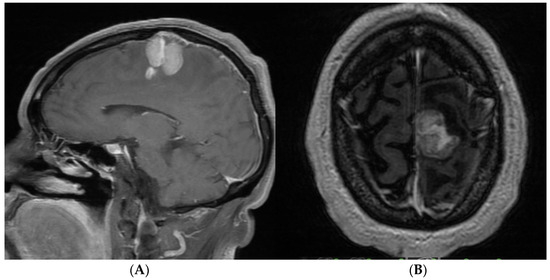

- Case 2: The AR-assisted transtentorial approach enabled near-total resection of a pineal region ependymoma, illustrating the technology’s efficacy in managing deep-seated tumors with complex vascular relationships; guided by AR to the pineal region where the tumor was located, in turn, AR allowed us to know the limits of the tumor; those limits were blocked to direct vision by the parenchyma and vascular structures (in-ferior sagittal sinuses, internal cerebral veins, basal of Rosenthal, vein of Galen, rectus, and inferior longitudinal sinus).